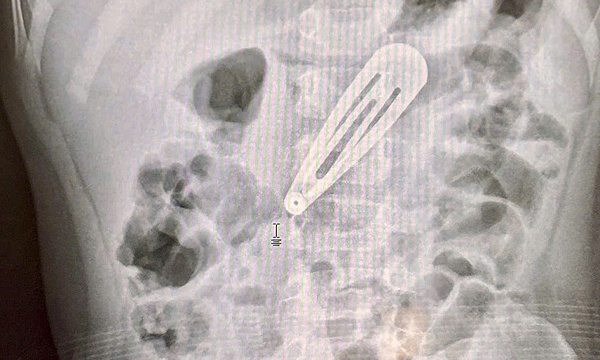

Gia đình đưa bé đến Bệnh viện Bệnh Nhiệt đới Trung ương cấp cứu, hôm 10/6. Kết quả chụp X-quang cho thấy dị vật kim loại nằm ở vị trí dạ dày. Các bác sĩ đã nội soi lấy kẹp tóc ra ngoài.

Theo bác sĩ Tô Duy Thư, dị vật là kẹp tóc kim loại, dẹt, cạnh sắc, nằm ở thân vị dạ dày. Dù kẹp không quá nhọn, kích thước lớn và cạnh sắc vẫn có thể gây rách hoặc thủng đường tiêu hóa, nhất là khi di chuyển đến ruột non.